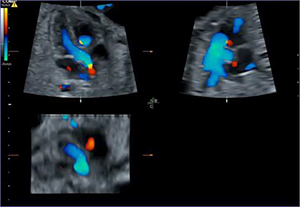

STIC(Spatio-Temporal Image Correlations)機能イメージ画像 |

「Voluson S10」は,Voluson E10とVoluson E8に採用されているプレミアム機種向けのシステムアーキテクチャ「Radiance System Architecture(ラディアンス・システム・アーキテクチャ)」で培った基盤技術をコンパクトなボディーに移植した「Voluson Core Architecture(ボルソン・コア・アーキテクチャ)」を採用した。このテクノロジーの搭載により,基本画質の向上,および心臓や血管の血液の流れをより繊細に装置のディスプレイ上で確認できる「カラードプラ」の感度向上を実現している。さらに,Voluson製品の強みである,3D/4D機能の性能も格段に向上。既に多くの施設で利用されているリアルな3D/4Dイメージング「HDlive」機能を始め,レンダリングのラインを自動でリアルタイムに最適化する「SonoRenderlive」機能,さらに,胎児の心臓の動きを再構築する「STIC(Spatio-Temporal Image Correlations)」機能を標準搭載するなど,周産期医療に必要な多くのアプリケーションを搭載し,日々の診療に貢献する。

正確に再現されたかのようなリアルな表現のサーフェス画像を表現し,仮想光源で陰影をつけることにより,さらなる立体感を実現した「HDlive」機能,胎児の心臓の撮影画像をボリュームデータとして 保存し,一定周期の繰り返し動作を行う対象に対して一周期分の3次元画像を再構築する「STIC(Spatio-Temporal Image Correlations)」機能,ボリュームデータ内の低輝度領域の数,容積,平均径を自動的に算出する「SonoAVCfollicle」(オプション)など, 周産期医療に特化したアプリケーションを豊富に搭載。